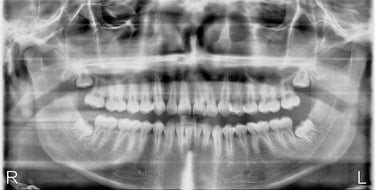

Before